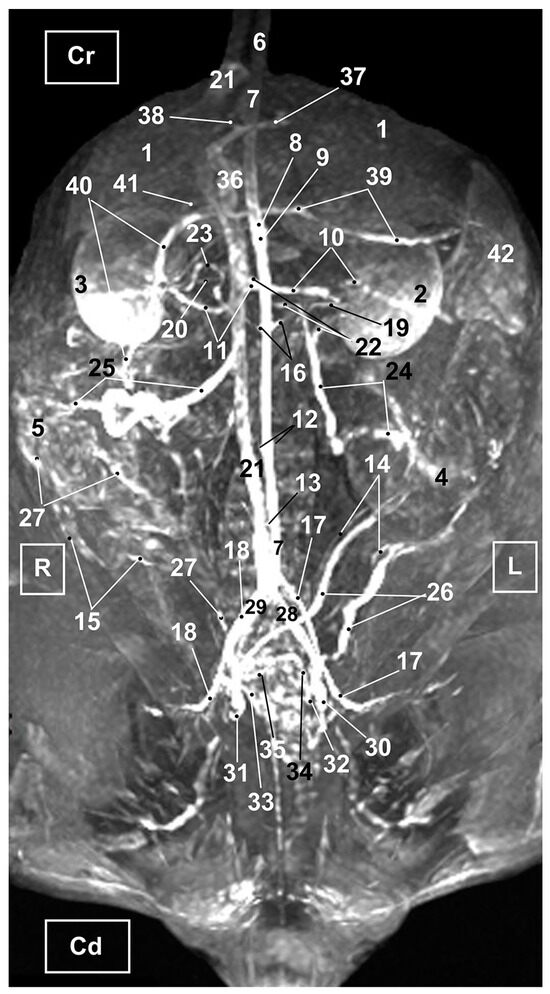

3.2. Computed Tomography Angiography and 3D Printing

3.2.1. Arterial System

3.2.2. Venous System